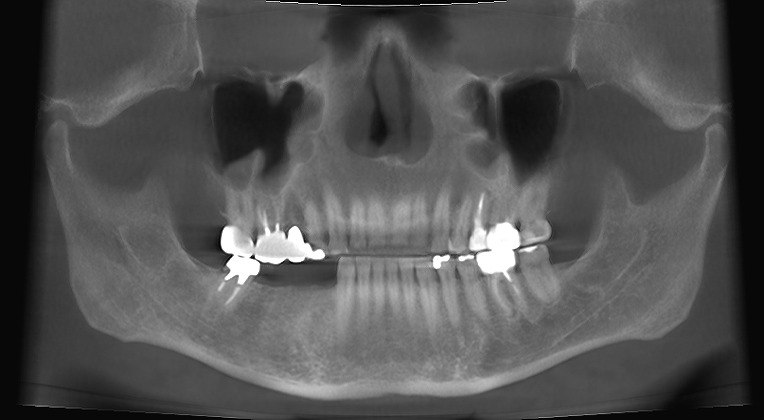

右下奥の欠損部にインプラント埋入を行っていきます 50代男性 入れ歯を作ったが入れれない 煩わしい インプラント考えたい

右下奥の欠損部にインプラント埋入を行っていきます 50代男性 入れ歯を作ったが入れれない 煩わしい インプラント考えたい

術前術後のパノラマになります